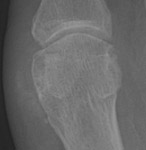

CPPD: AP - Faint calcifications at 1st MT headCPPD: AP - Faint calcifications at 1st MT head CPPD DISEASE (PSEUDOGOUT) calcium pyrophosphate dihydrate deposition within cartilage and peri-articular structures.

Variable, inconsistent osteophyte formation can occur with this disease. Numerous, large subchondral cysts may progress to micro fractures, collapse, and formation of intra-articular bodies. Calcific tendonitis (especially of the Achilles tendon and plantar aponeourosis), or metatarsophalangeal joint capsular or synovial calcifications may be present. Associated calcifications of the bursa, ligaments, and fibrocartilaginous structures of the foot are less common.